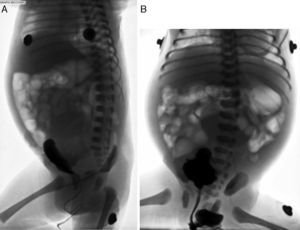

En la cistouretrografia se observó rechazo de la vejiga hacia adelante por una masa densa no dependiente ni relacionada con las vías urinarias, descartándose quiste del uraco y megavejiga; no había reflujo vésico-ureteral ni valvas uretrales (fig. 4). Se consideraron los diagnósticos de hidrometrocolpos y, menos probablemente, de quiste ovárico. Se complementó con resonancia magnética, la cual confirmó un hidrometrocolpos con efecto compresivo sobre las vías urinarias (fig. 5).

Cistouretrografía miccional. A. Proyección lateral en la que se observa la vejiga con medio de contraste, rechazada hacia Adelante por una masa densa no dependiente ni relacionada con las vías urinarias. B. Proyección anteroposterior durante la micción, en la cual se descartan reflujo vésico-ureteral y valvas uretrales.